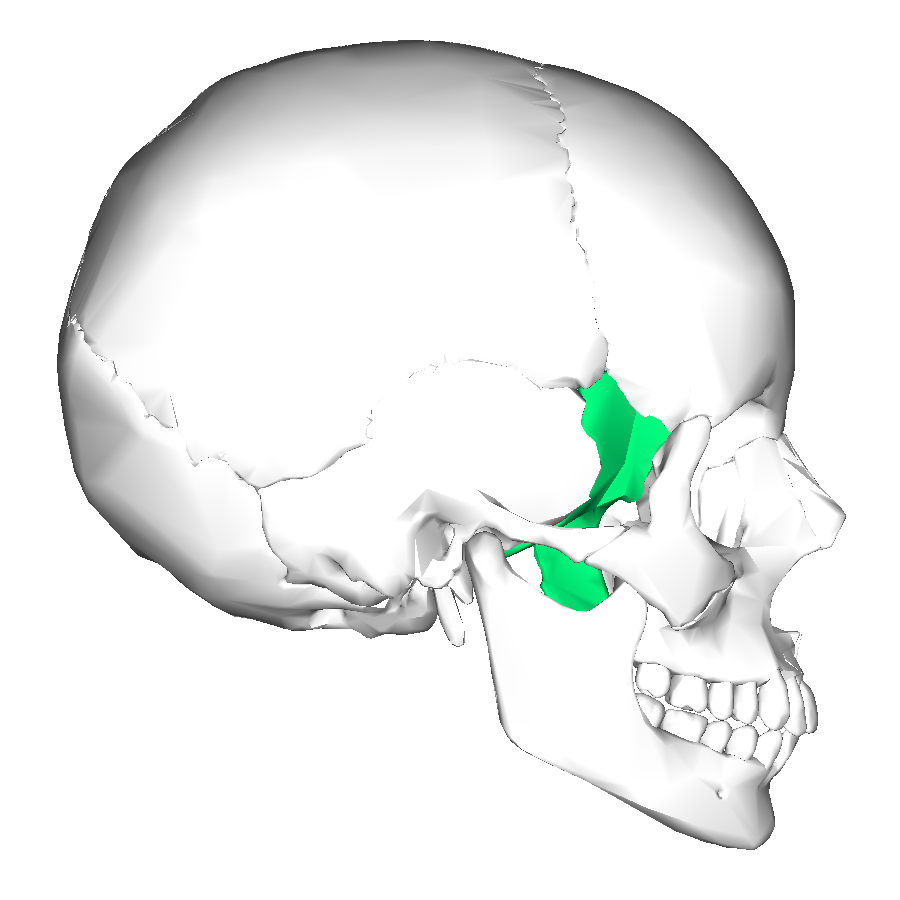

What is this region?

Temporal Bone